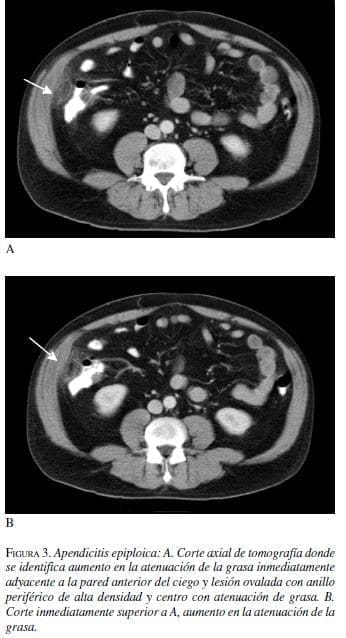

Hombre de 41 años con cuadro de 24 horas de dolor en la fosa iliaca derecha. Leve aumento en la velocidad de sedimentación globular y leucograma normal. Con impresión diagnóstica dudosa de apendicitis aguda se realiza tomografía contrastada de abdomen (figura 3).

Los apéndices epiploicos son normalmente invisibles en la tomografía a menos que estén rodeados por ascitis. Los hallazgos característicos de apendicitis epiploica son: una masa oval paracolónica con densidad de grasa que representa el apéndice inflamado o infartado, con aumento en la atenuación de la grasa a su alrededor, un anillo hiperatenuante bien definido que rodea a la masa que representa al peritoneo visceral inflamado y en algunas ocasiones un “punto” central de alta atenuación que representa los vasos ingurgitados o trombosados o áreas centrales de hemorragia (3, 8-9).